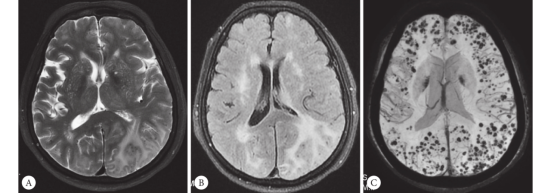

走进上海华山医院神经内科门诊,候诊椅上总是坐满拿着影像报告颤抖的家属。我国60岁以上人群阿尔茨海默病患病率达5.7%,但残酷的现实是:

"我们正在建设专用输注中心。"北京天坛医院副院长透露,首批20家三甲医院将开展用药培训,需进行PET确认淀粉样蛋白沉积的患者才能用药。